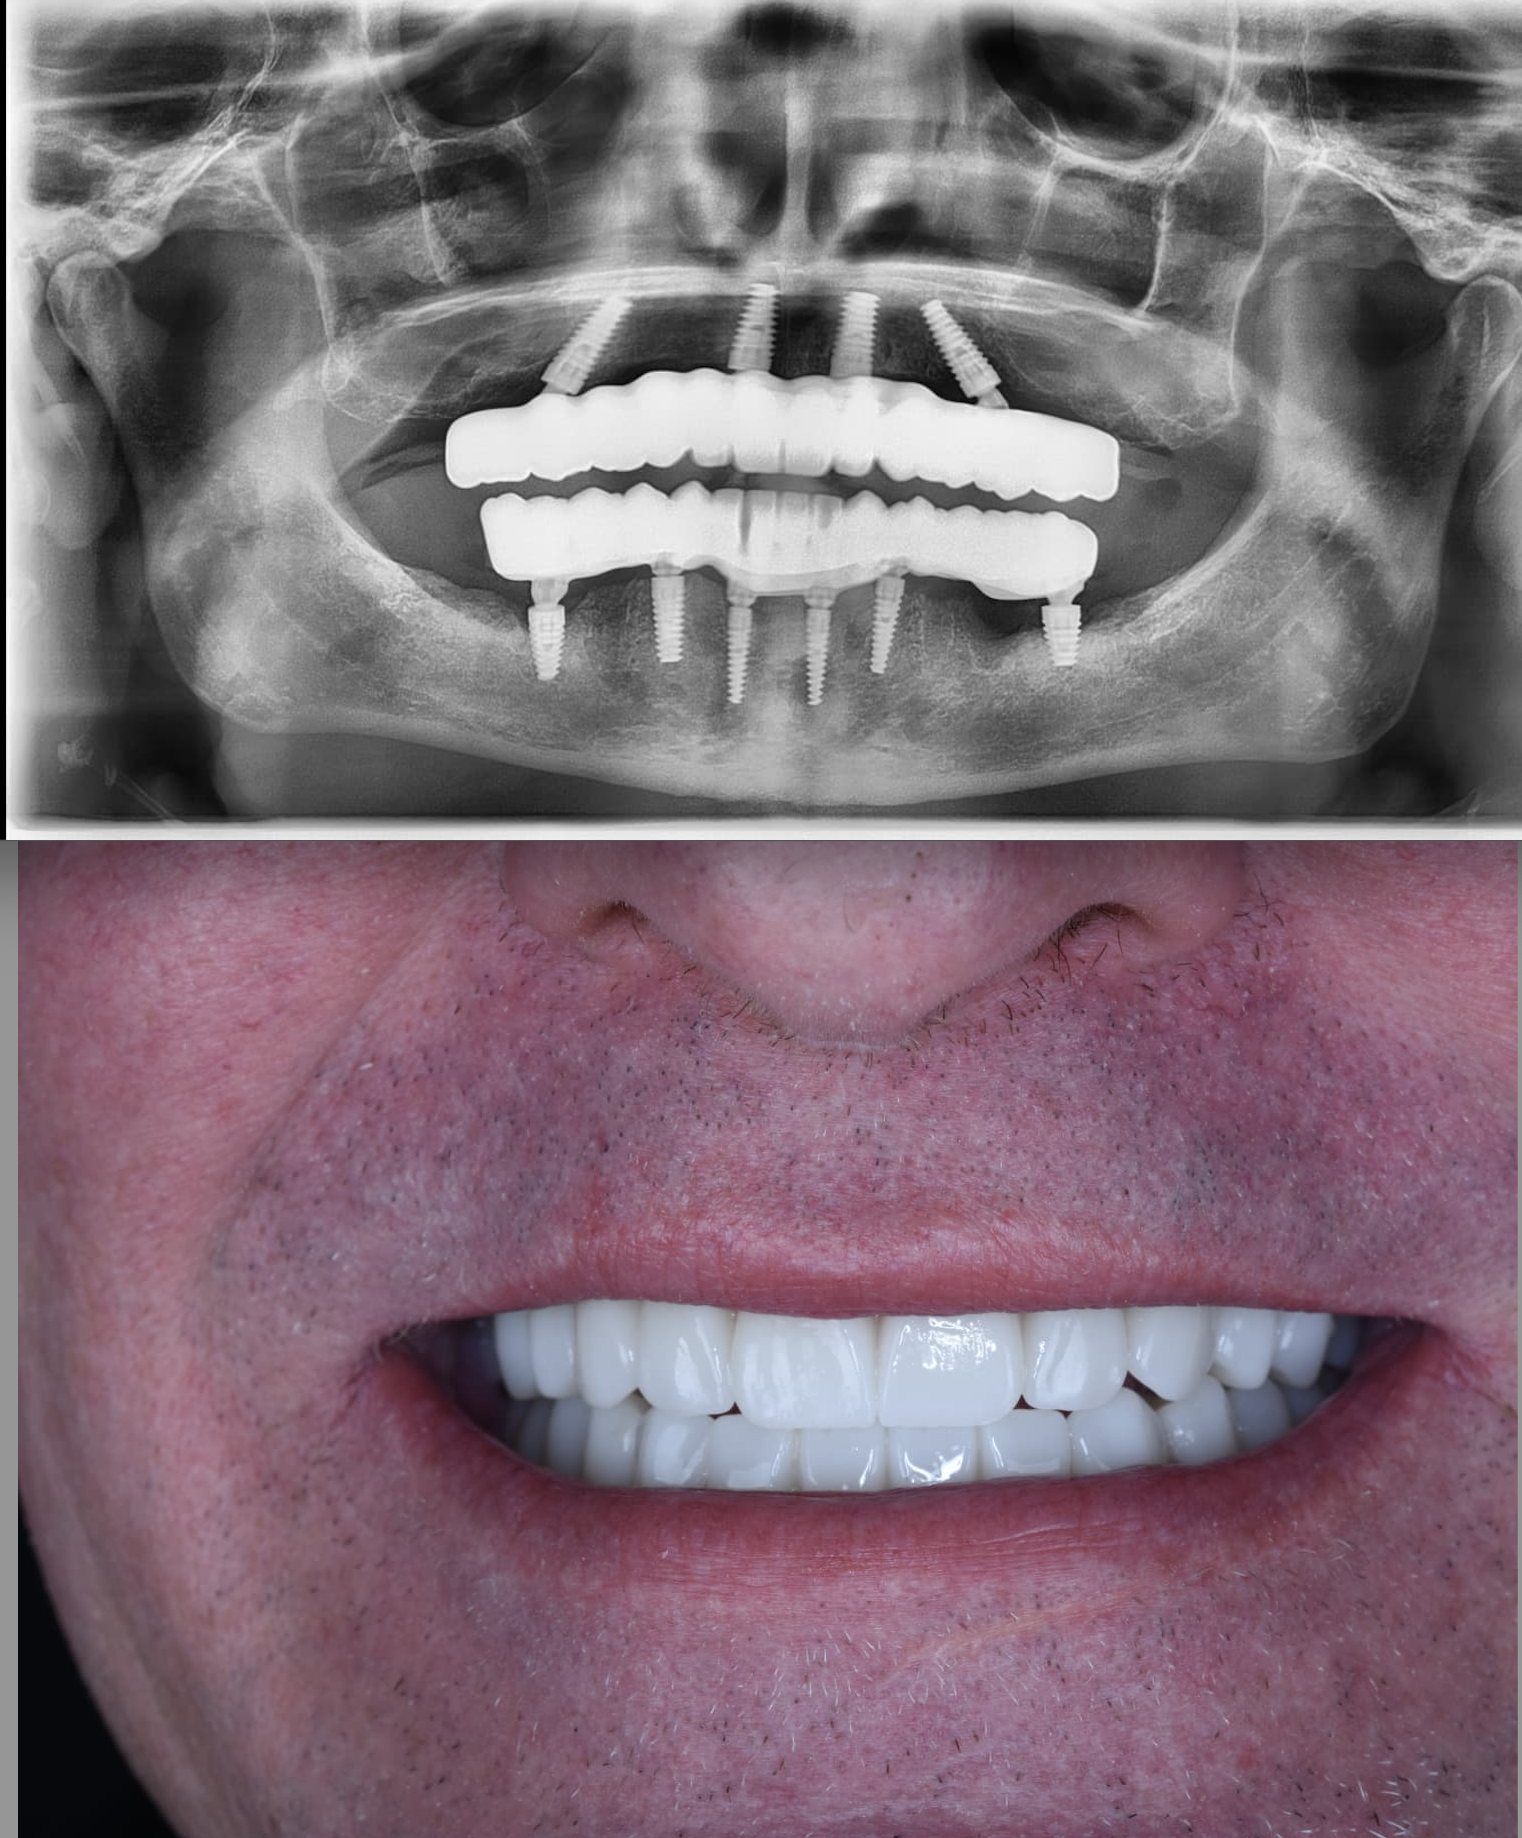

Zygomatic Implants Case Study

Case Study

Advanced Zygomatic

Implant Rehabilitation

Fixed prosthetic rehabilitation with zygomatic implants for a patient presenting with extreme bone deficiency and failed previous implant attempts from another facility.

In this complex case where traditional implant treatments were technically impossible to apply, the ZAGA Concept allowed us to provide a stable, long-term solution through specialized zygomatic surgery, restoring both function and aesthetics.

• Removal of failed implants from external centers

• Severe bone loss management via Zygomatic Concept

• Full functional and aesthetic fixed restoration